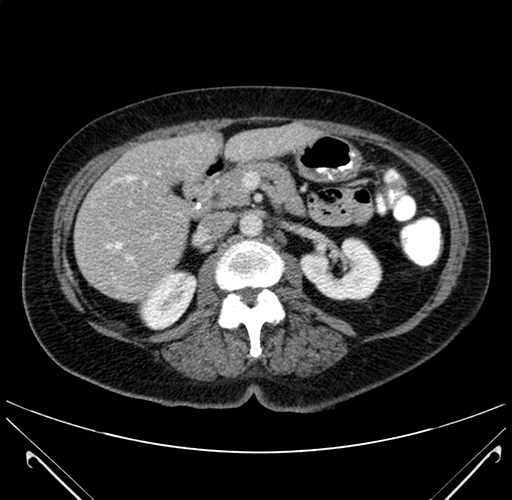

Pre-Chemo: Axial Venous

Axial Venous